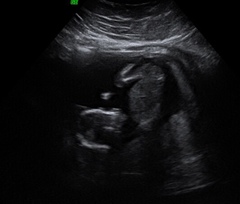

dreaminofholidays · 28/09/2018 17:19

@jessabean what a lovely scan photo. Very pleased for you!

So, I’ve had my 12 week scan today. I was dreading it, cried all the way there. But it went really well, everything is looking good and we’re measuring ahead of what we thought at 13+3 making my new due date 2nd April. Can’t actually believe it!!!